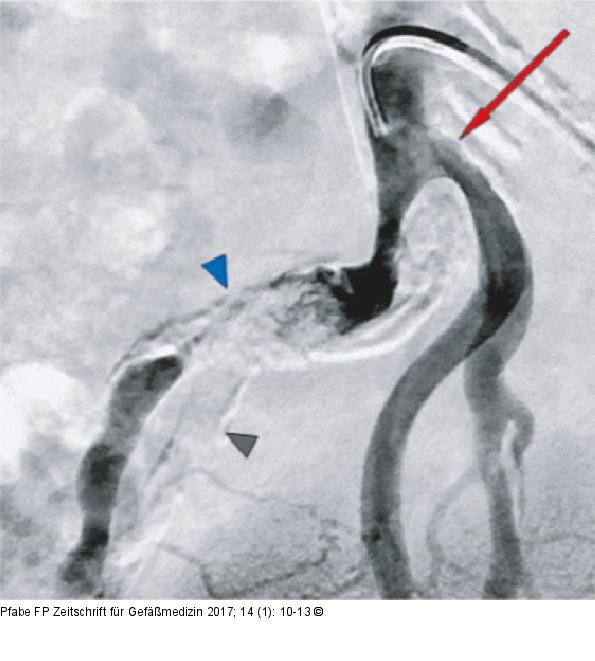

Abbildung 2: Beckenübersicht DSA-Angiographie der Beckenarterien rechts. Leichtgradige Stenose der Nierenarterie rechts (roter Pfeil), schwer kalzifiziertes Verschlusssegment (blauer Pfeil), Kalkschatten der verschlossenen A. iliaca interna (grauer Pfeil). |

Abbildung 2: Beckenübersicht

DSA-Angiographie der Beckenarterien rechts. Leichtgradige Stenose der Nierenarterie rechts (roter Pfeil), schwer kalzifiziertes Verschlusssegment (blauer Pfeil), Kalkschatten der verschlossenen A. iliaca interna (grauer Pfeil). |